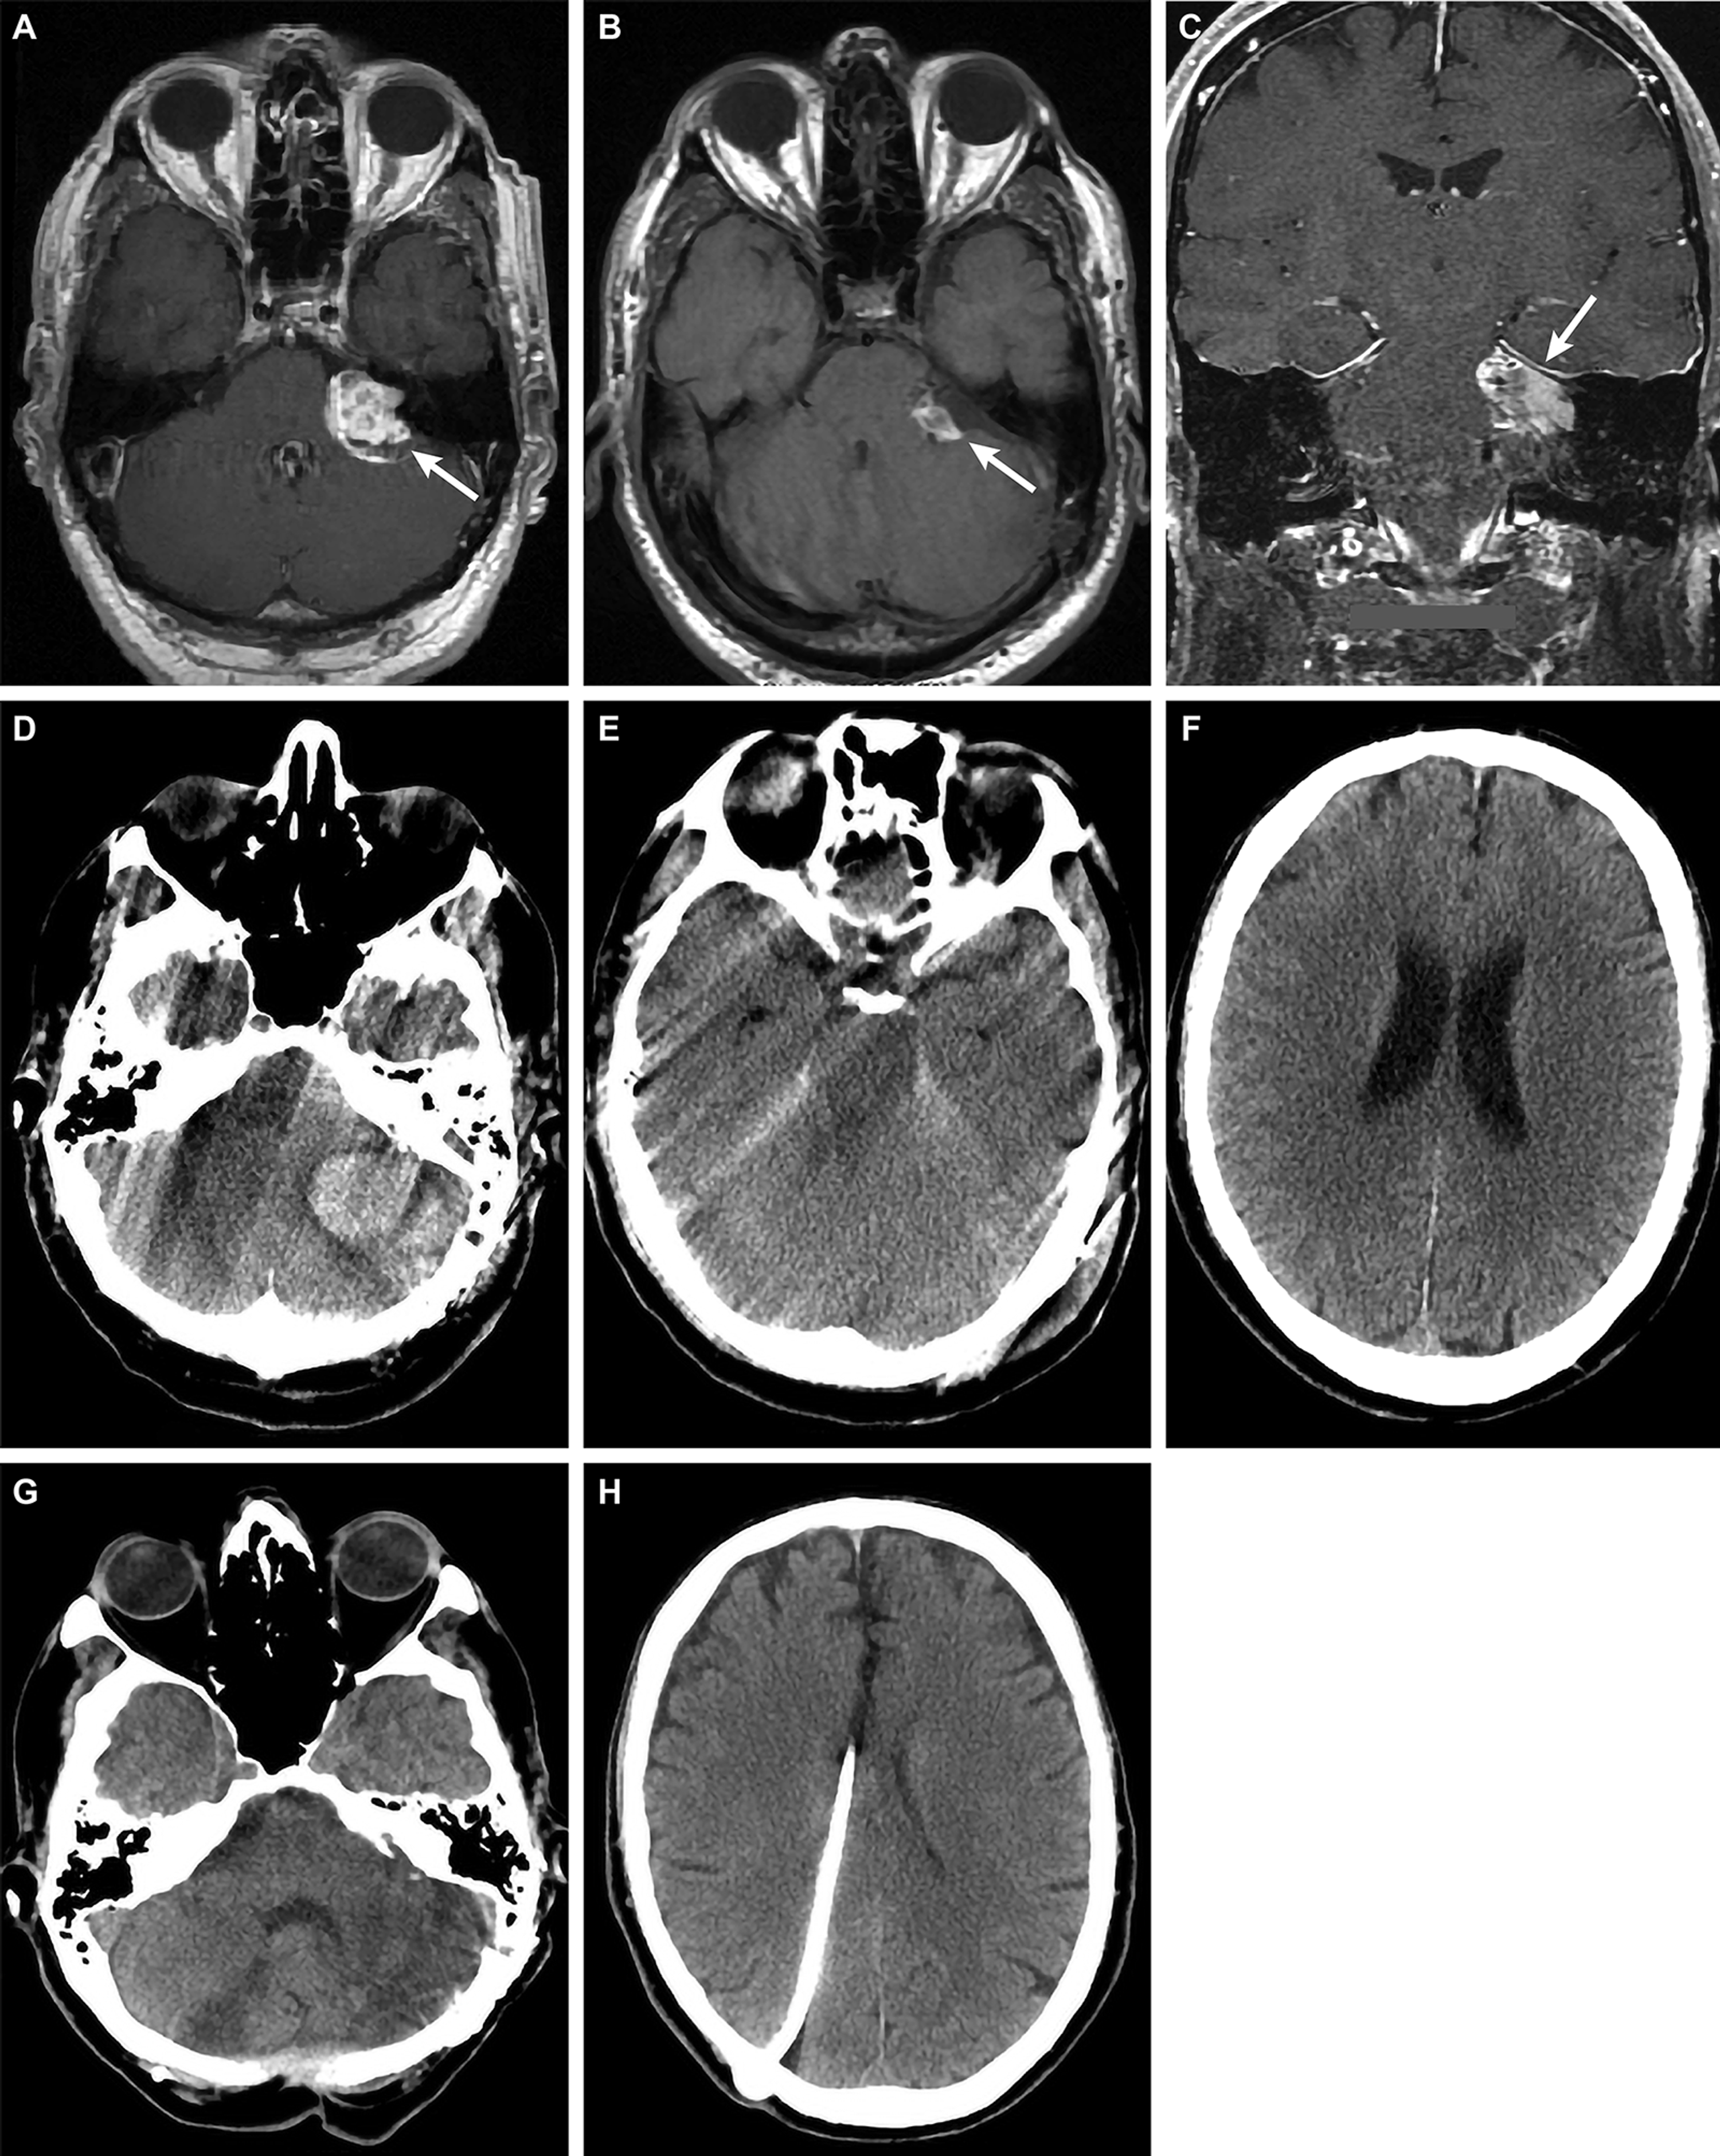

Cureus Posterior Fossa Hemorrhage Following The Use Of Low Molecular Weight Heparin Lessons Learned And Recommendations For The Treatment And Prophylaxis Of Postoperative Venous Thromboembolism